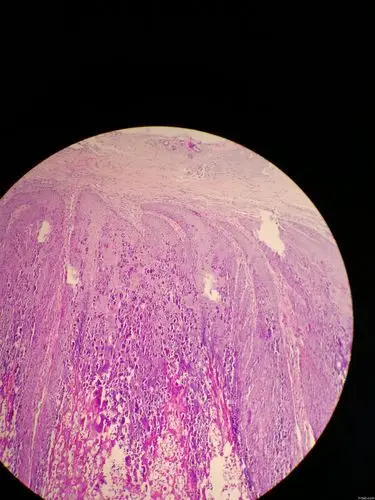

跖疣?讨论病例【91360.软组织348】 - 软组织病理 - 91360病理论坛